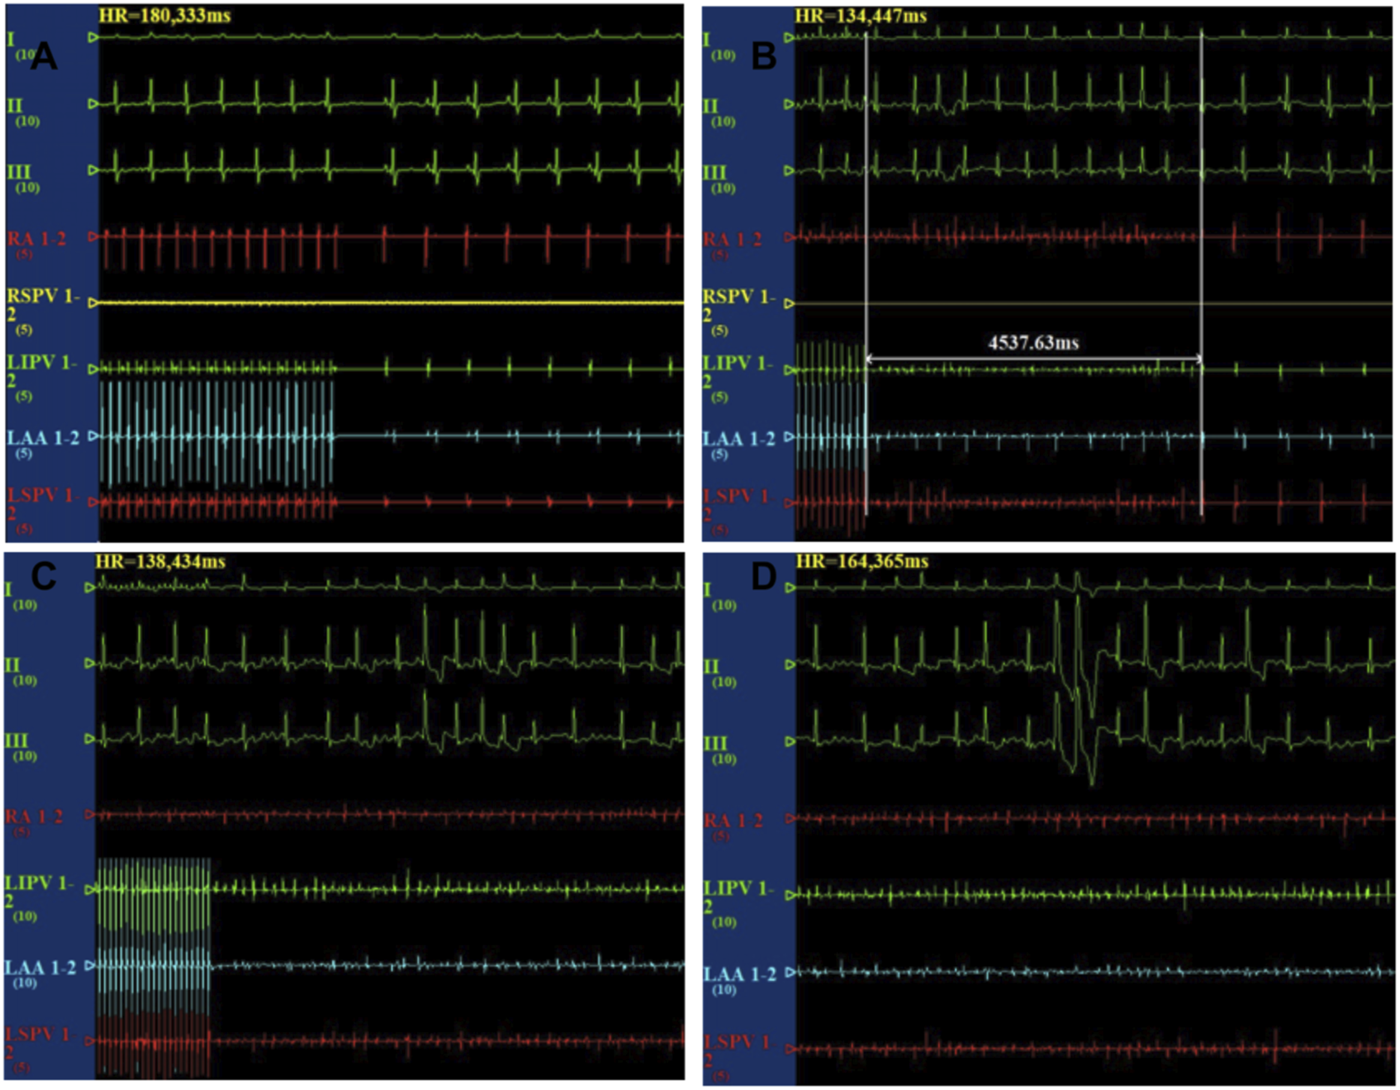

After the cessation of 6 h pacing, the mean AF times (4.8 ± 1.7 vs 0.17 ± 0.4, p < 0.001) and the AF duration (48.9 ± 39.9 vs 1.1 ± 2.7 s, p < 0.05) were higher in the pacing group when compared with the baseline. However, there was no change in the mean AF times (0.17 ± 0.4 vs 1.2 ± 2.9 times, p > 0.05) and the AF duration (1.0 ± 2.4 vs 7.6 ± 9.7 s, p > 0.05) between the baseline and after 6 h pacing in the TRAM-34 group. The mean AF times (0.33 ± 0.81 vs. 4.8 ± 1.7 times, p < 0.05) and AF durations (3.6 ± 8.6 vs 48.9 ± 39.9s) were increased in the RAP group compared with control group. The mean AF times (1.2 ± 2.9 vs 4.8 ± 1.7s, p < 0.05) and AF durations (7.6 ± 9.7 vs 48.9 ± 39.9 s, p < 0.05) were lower in the TRAM-34 group compared those with the RAP group. The representative ECG pictures were shown in Figure 4.

FIGURE 4. Representative picture of AF induction in the three groups. In the control group, the burst pacing didn’t induce AF (A). In the TRAM-34 group, after 6 h pacing, the burst pacing didn’t induce AF (B). In the RAP group, after 6 h pacing, the burst pacing induced AF last for 21.3 s (C,D).